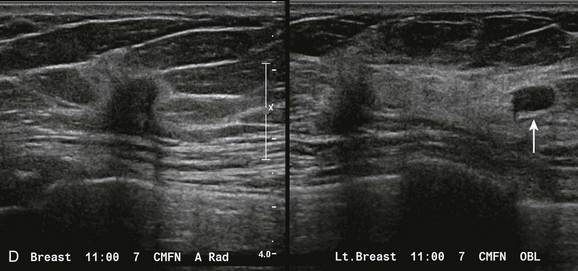

CASE 8-9. A 41-year-old woman with a history of bilateral cysts had screening mammography performed 2 months ago that showed extremely dense tissue with multiple bilateral benign-appearing masses. There were no suspicious findings (BI-RADS 2).

She now presents with a new palpable mass in her upper right breast and is referred for US. Your sonographer brings you the following images from the palpable region. What do you recommend?

CASE 8-9. There are multiple cysts. Did you notice the hypoechoic shadowing region on the lower right image? You rescan this region and find a hypoechoic solid shadowing mass with spiculated margins, adjacent to cysts. This is highly suspicious. Diagnosis: IDC.